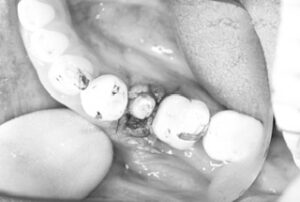

切開、抜歯から埋入、縫合までの全てを20分で終了。

その後は密着具合を示す値も良く、即日に仮歯まで装着してお帰り頂きました。